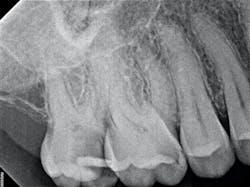

In the case below, tooth No. 2 was diagnosed with symptomatic irreversible pulpitis and symptomatic apical periodontitis with a mesial marginal ridge fracture due to extensive caries (figure 1). Root canal therapy and a full coverage crown were recommended and the patient accepted.

The iTero scanner was able to clearly define the delineation between the soft and hard tissue as can be seen in this image of the digital die trim (figure 3). Radiographs were captured on delivery revealing a clinically acceptable outcome for the patient (figure 4). Direct restorations were completed on teeth Nos. 3 and 4 during this visit.